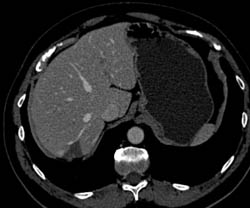

Gastric Varices With Splenic Vein Occlusion